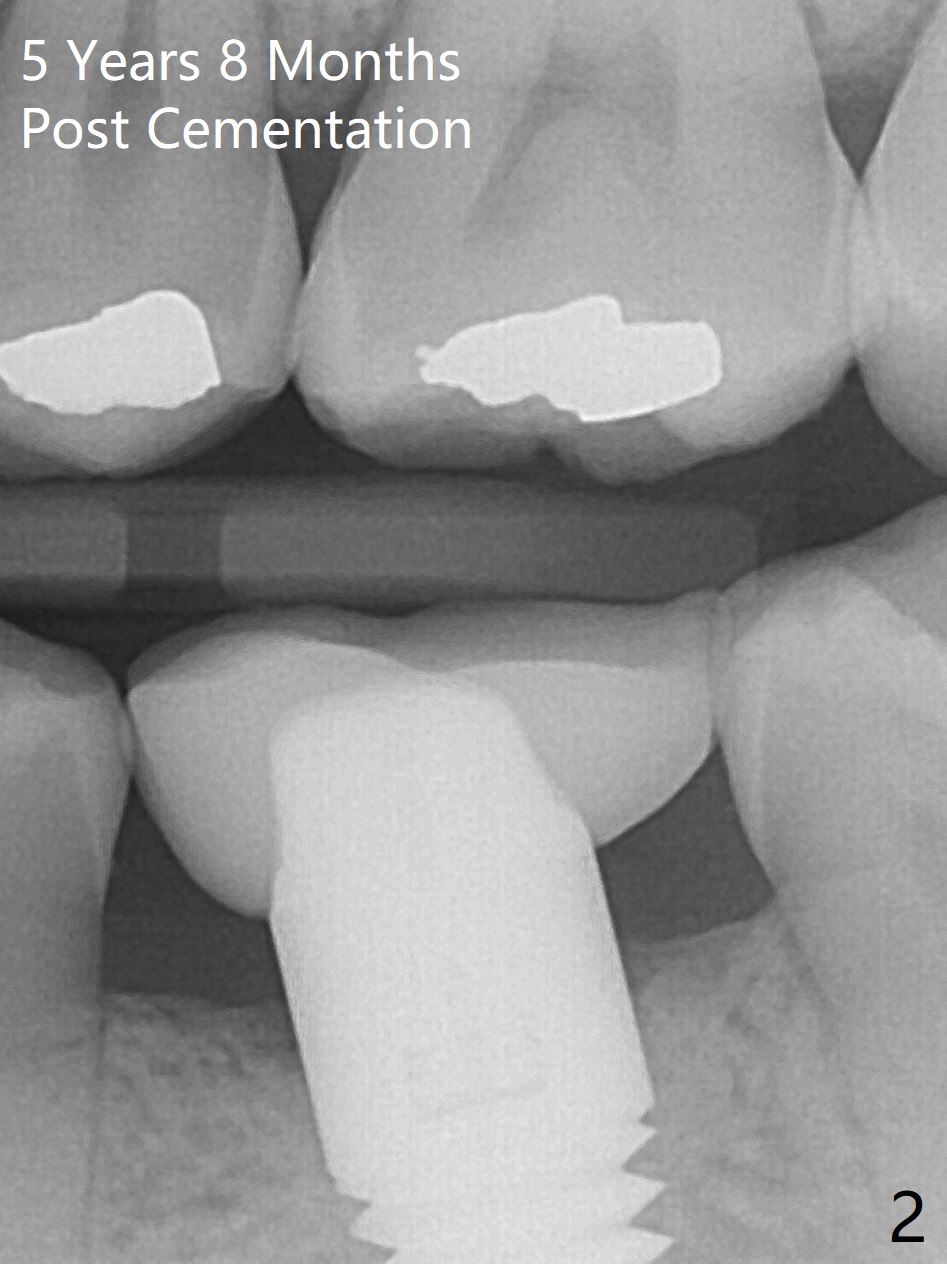

A 29-year-old man returns for follow up 5 years 8 months post cementation of the crown at #19 (Fig.1; 2 (bitewing)). The bone density around the coronal end of the 6x17 mm tissue-level implant (8 months post extraction without socket preservation) is high (*). Why is the implant crown (C) short?